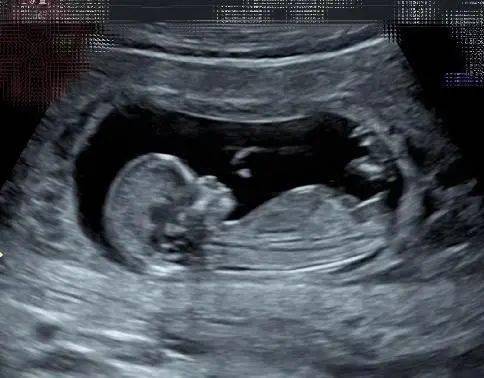

孕妇在进行B超检查时,需要注意以下几点首先,孕早期进行B超检查需要膀胱内积聚一定量的小便,以便能更清晰地观察,所以应提前憋尿但到了孕3个月后,随着宝宝的成长,这一需求就不再存在,可以随去随做其次,避免在饥饿状态下进行B超检查,特别是孕中晚期,如果宝宝不配合,可能会导致某些数据无法。